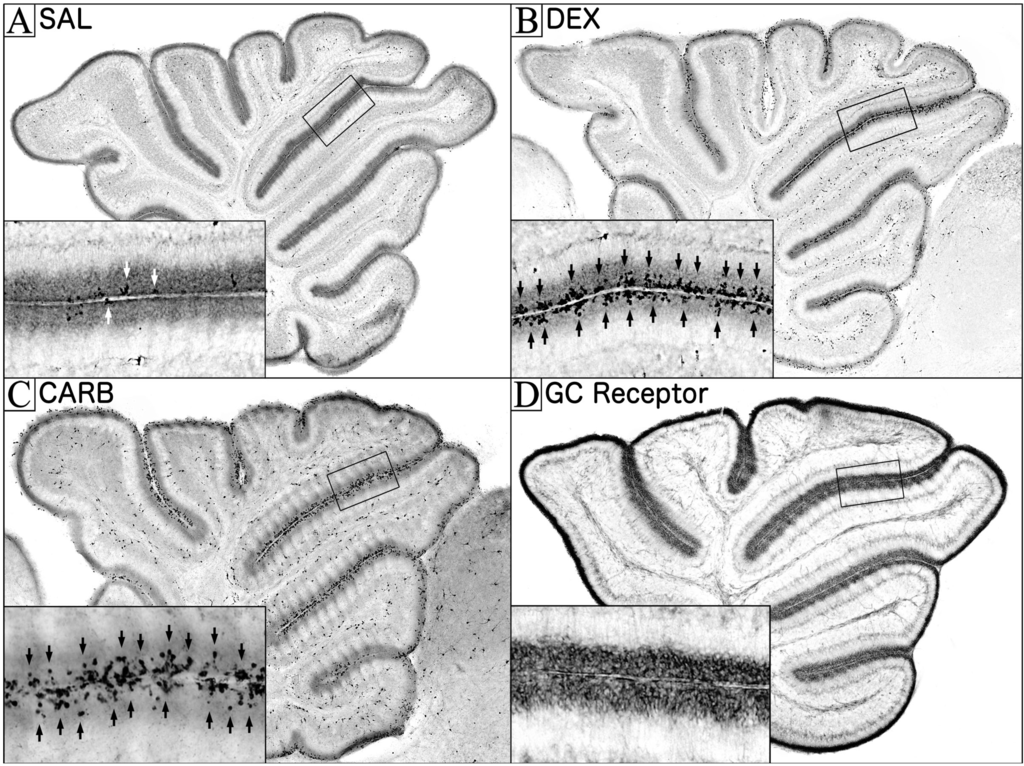

Figure 1. Glucocorticoid receptor stimulation in the neonatal rodent cerebellum. (AC) Immunolabeling in the midsaggittal mouse cerebellum with the apoptotic marker activated caspase-3, six hours after saline (SAL), 3.0 mg/kg dexamethasone (DEX), or 100 mg/kg carbenoxolone (CARB). (A) SAL treated animals exhibited low amounts of physiological apoptotic death (white arrows), whereas (B) DEX treated animals exhibited dramatic increases in apoptosis (black arrows) throughout the EGL; (D) Simply, inhibiting HSD2 (an enzyme which metabolizes and protects against certain GCs) with 100 mg/kg carbenoxolone (CARB) rapidly increases NPC apoptosis in the EGL (black arrows). This suggests that when HSD2 is present, it is constantly preventing endogenous GC stimulation from producing EGL apoptosis. (C) Immunolabeling with the GC receptor antibody M20 reveals GC receptors are densely located in the EGL of the PND7 neonatal mouse. Insets reflect magnified views of boxed regions.

If GC’s signal the removal of the EGL, the body would need to maintain intricate regional and temporal control over endogenous stimulation in order for the cerebellum to develop correctly. One of the first indications of this is GC receptor expression. Pavlik et al. [49] showed that the rodent neonatal cerebellum has GC receptor levels more than three times higher than any other region of the brain. Interestingly, these receptor levels increased as the EGL was expanding but decreased as the EGL was disappearing, suggesting a large portion were localized to the EGL. In order to determine what cerebellar sublayers contain these receptors, we performed GC receptor immunohistochemistry and discovered that the highest concentration, by far, was in the EGL (Figure 1D) [20].

A final way the body can regulate endogenous GC stimulation is through the expression of the enzyme 11β-Hydroxysteroid Dehydrogenase Type II (HSD2), which selectively protects tissue from GC stimulation by rapidly inactivating endogenous GCs before they can stimulate GCs receptors [52,53]. This enzyme is thought to be involved in neurodevelopment due to its high expression throughout the rodent brain in early gestation [55]. Around mid-gestation, levels in the brain decrease rapidly until HSD2 is almost exclusively isolated to the EGL at birth. As the neonate ages, high HSD2 levels are maintained until disappearing as the EGL is naturally eliminated from the cerebellum [52]. In order to test whether this natural decrease in HSD2 might contribute to the disintegration of the EGL, this enzyme was inhibited in neonatal mouse pups and the cerebella were screened for apoptosis. The results revealed that simply inhibiting this enzyme during the stress hyporesponsive period dramatically increased NPC apoptosis within a few hours (Figure 1C) [19]. It was also found that this toxicity could be blocked by pretreatment with GC receptor antagonist suggesting it is produced through endogenous GC stimulation [19]. These results suggest that, during the stress hyporesponsive period, HSD2 is constantly protecting the EGL from apoptosis. Interestingly, the ability of HSD2 to protect the EGL may have important implications for perinatal GC therapy. This is because HSD2 is efficient at protecting against endogenous GCs, such as hydrocortisone (Note: when the endogenous GC cortisol is administered as a drug it is often called hydrocortisone), but has a very limited ability to protect against the most commonly used synthetic GCs (e.g., dexamethasone and betamethasone). As a result, many synthetic GCs bypass the natural protection afforded by HSD2 in the EGL. Consistent with this idea, equipotent doses of endogenous GCs produce less NPC apoptosis than dexamethasone or betamethasone [19]. It should be noted that, while the HSD2 enzyme is also regionally expressed in the lungs, it is not present in the alveoli, which contain surfactant producing cells (type II pneumocytes) that improve respiratory function [56]. As a result, using endogenous GCs, such as cortisol (i.e., hydrocortisone), may allow HSD2 to selectively protect the EGL while allowing the therapeutic effects on lung maturation to occur. Consistent with this concept, recent research found increasing HSD2 expression in the EGL reduced GC induced EGL apoptosis [57].